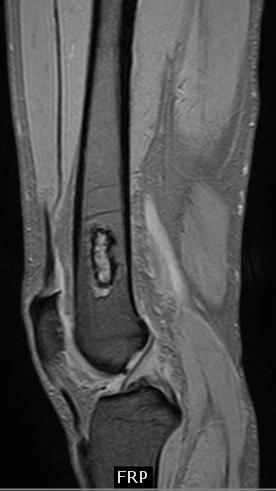

Инфаркт кости коленного сустава на МРТ: диагностика и лечение